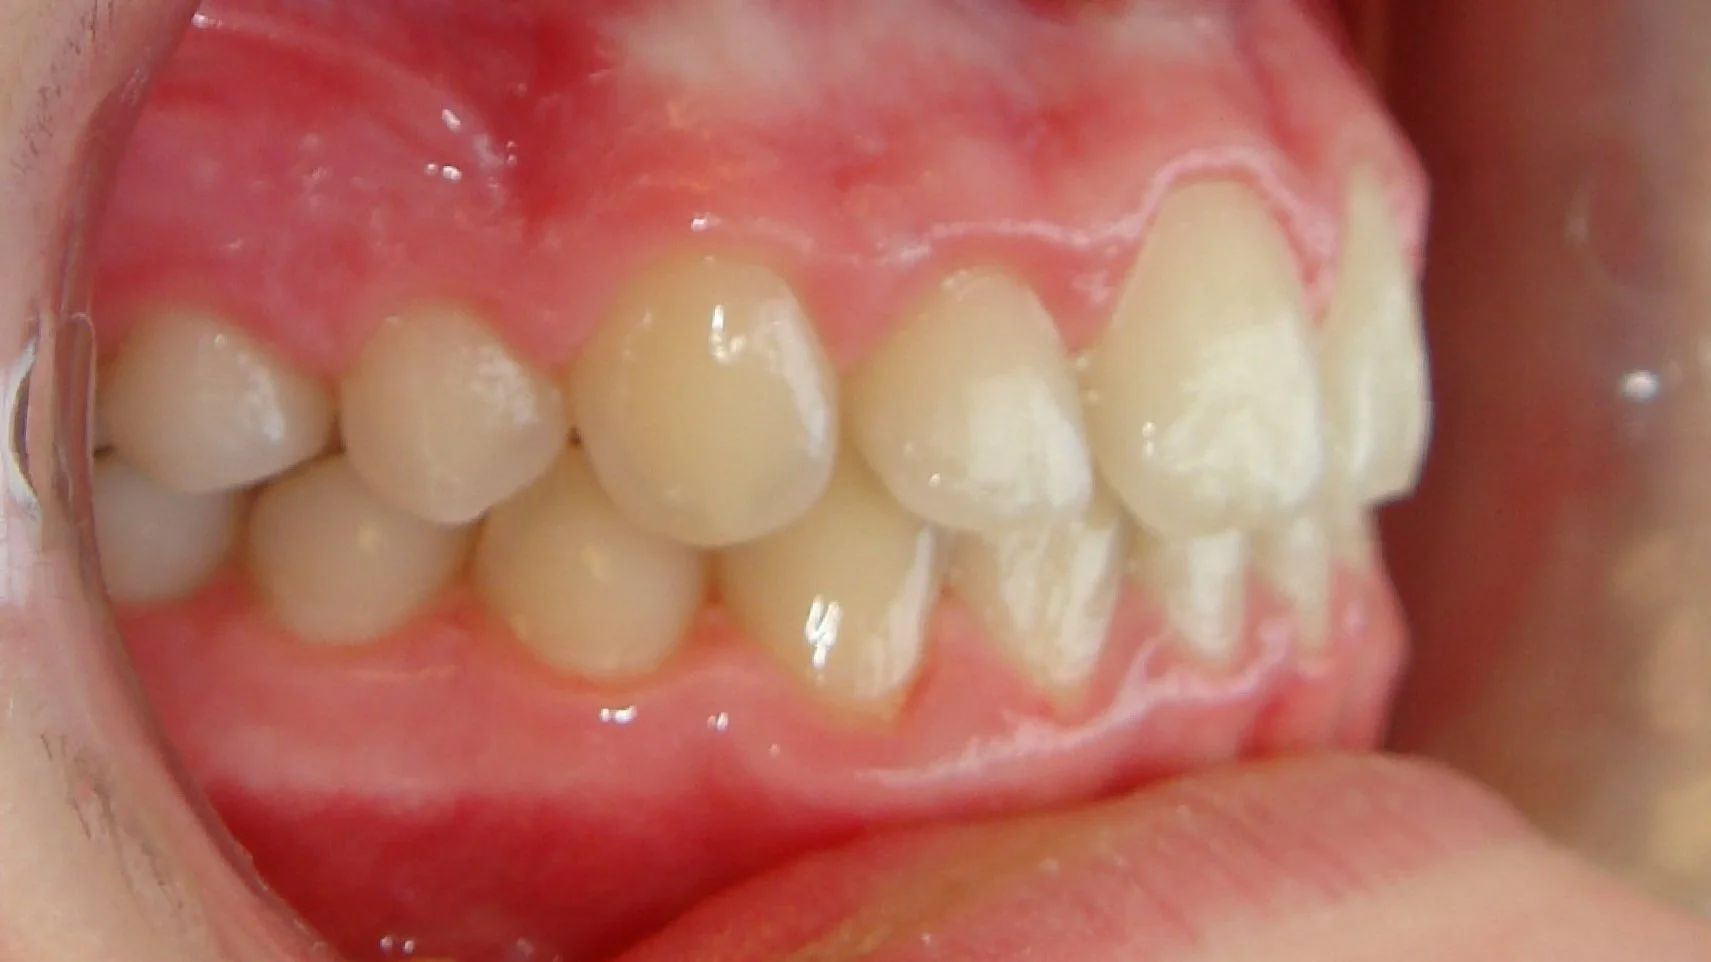

After

Close-up side view of human teeth and gums showing ideal alignment and occlusion.

This 10 year old girl had crowding of her upper and lower teeth, and an extreme overjet and overbite. Her case was treated over 2 years with braces and elastics.